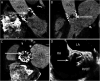

Infective Endocarditis (IE) remains a significant health challenge. Despite an increasing awareness, mortality is high and has remained largely unchanged over recent decades. Early diagnosis of IE is imperative and to assist clinicians several diagnostic criteria have been proposed. The best known are the Duke criteria. Originally published in 1994, these criteria have undergone significant modifications. This manuscript provides a timeline of the successive changes that have been made over the last 30 years. Changes which to a large degree have reflected both the evolving epidemiology of IE and the proliferation and increasing availability of advanced multi-modality imaging. Importantly, many of these changes now form part of societal guidelines for the diagnosis of IE. To provide validation for the incorporation of cardiac computed tomography (CT) in current guidelines, the manuscript demonstrates a spectrum of pictorial case studies that re-enforce the utility and growing importance of early cardiac CT in the diagnosis and treatment of suspected IE.